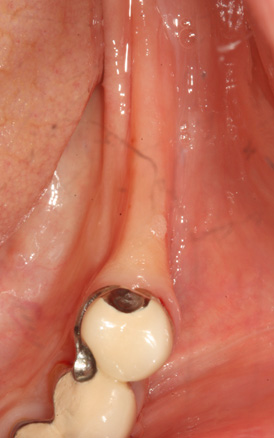

청담네오플란트 원데이 임플란트

하루만에 발치와 임플란트 식립을 동시에!

일반적으로 살릴 수 없는 치아를 발치하면, 2~3개월의 잇몸뼈 회복기를 거친 후 임플란트를 식립하게 됩니다. 하지만 잇몸뼈의 소실이

심하지 않은 경우 임플란트의 전체 치료기간 단축과 환자분의 불편감을 최소화하기 위해 내원 당일 발치 및 임플란트 식립을 진행할 수 있습니다.

필요에 따라 치조골 이식이 필요할 수 있으며, 가능한 경우 당일 임시 보철물 장착까지 해드려 심미적 기능을 회복할 수 있습니다.